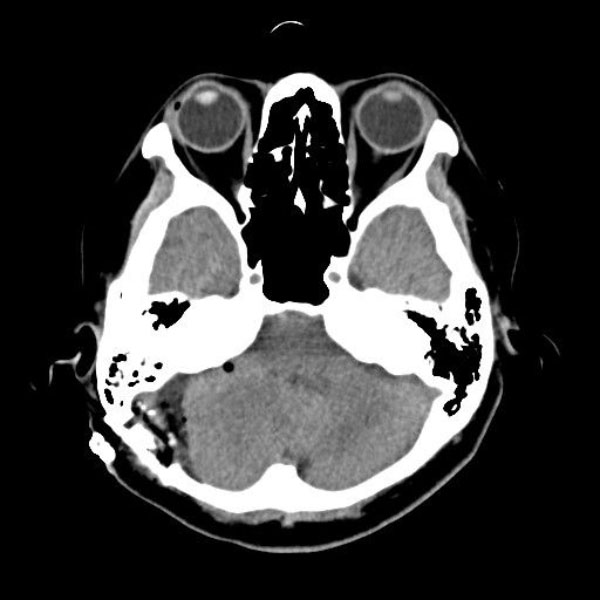

手術後

(CT)